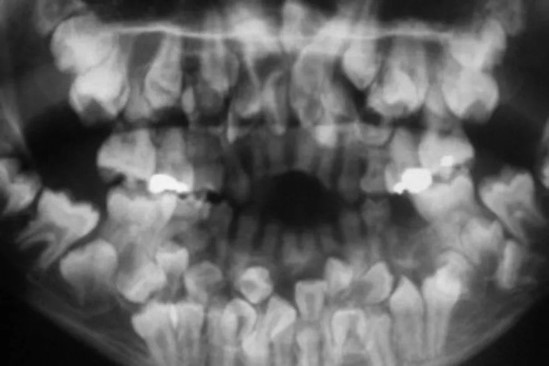

A través de una tomografía computarizada, los especialistas comprobaron que, de estos 81 dientes, 18 eran caducos, 32 permanentes y 31 supernumerarios, los cuales pueden aparecer en cualquier zona de la arcada. La tomografía mostró, además, un claro ramillete de dientes a ambos lados de la boca de la paciente, que se repartían a lo largo y ancho de todo el maxilar superior y la mandíbula.